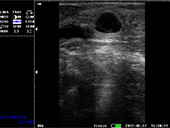

牛受孕泡

牛受孕35天